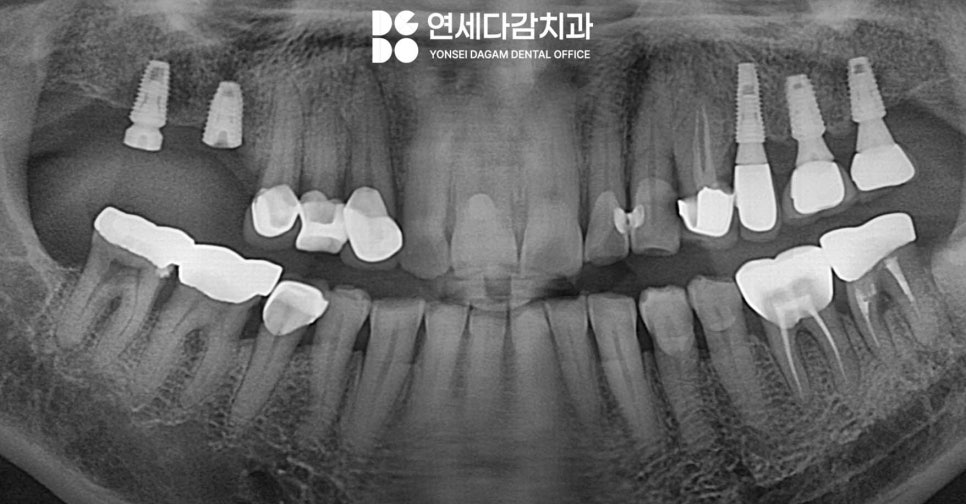

따라서 가락시장역 치과 에서는

정확한 검진이 필요하기 때문에

엑스레이를 촬영하는데,

이 과정에서 가락시장역 치과 에서는

환자의 구강 습관을 파악하기도 합니다.

평소 이를 악무는 습관이 있는지

자면서 이갈이를 하는지 확인하는 것이죠.

또한 저작력이 강한 특징을 가진 경우

구강 전체를 살펴봤을 때 전반적으로

치아 마모가 진행되어

치아 표면이 평평하게 닳아있는 모습을

보일 때가 많습니다.